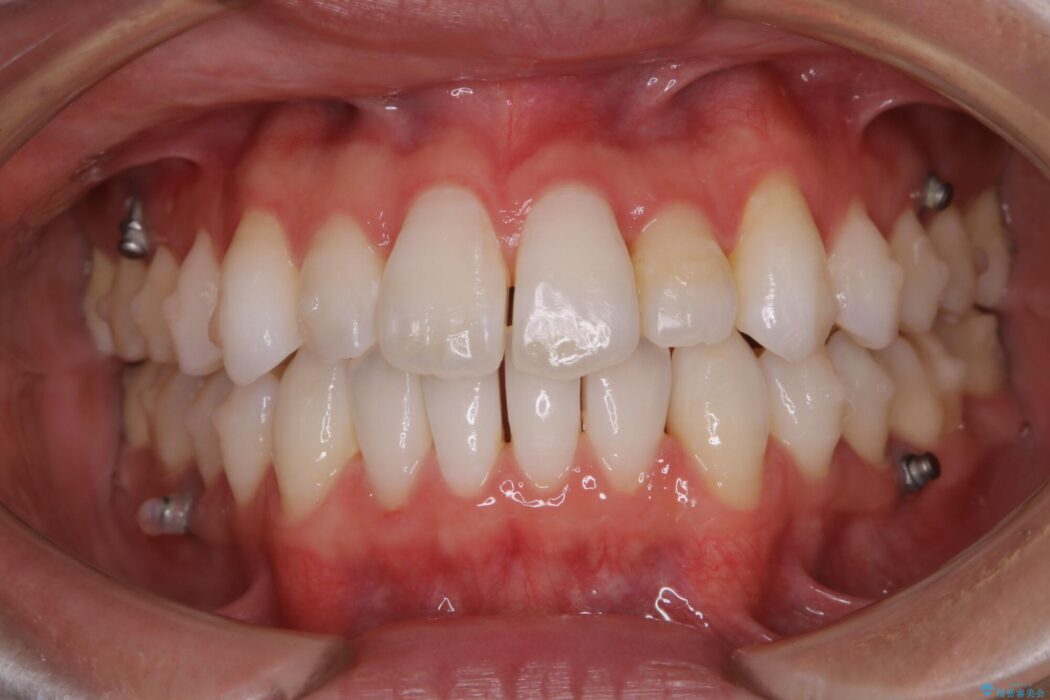

【20代男性】上顎のガタガタな歯列をインビザラインで矯正治療

前に出ていた前歯や目立つ八重歯(3番目の歯)もきれいに並び、奥歯の虫歯治療も並行して行ったため、機能面でも見た目的にも良くなり満足していただきました。

本症例では上記3つの方法を複合的に組み合わせた治療を行いました。